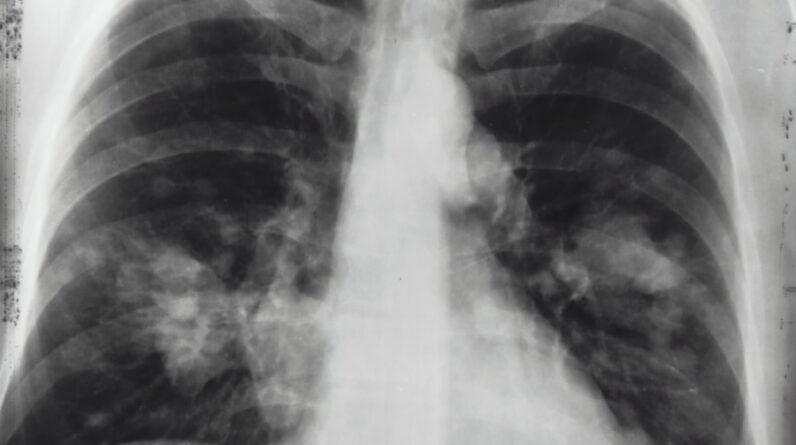

Diagnosis of mesothelioma often involves imaging tests such as X-rays and CT scans, as well as biopsy to examine tissue samples for the presence of cancer cells.